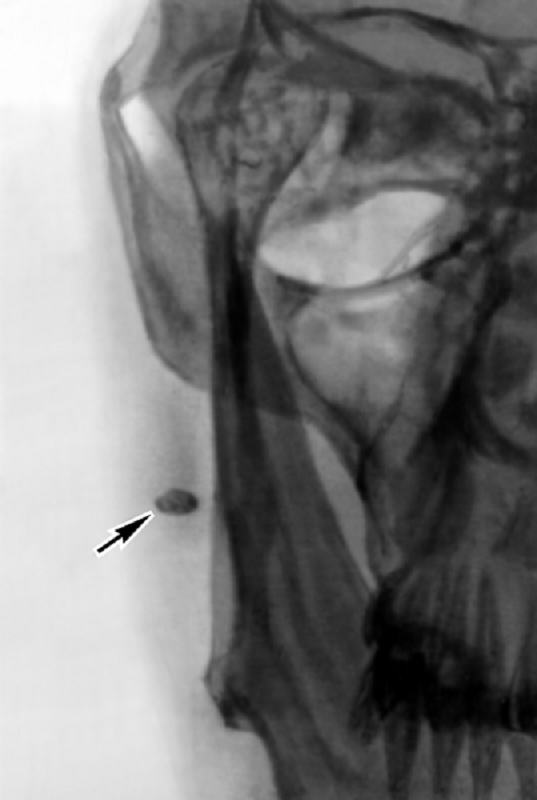

Сущность литотрипсии заключается в том, что ударные волны, создаваемые электромагнитной катушкой генератора в жидкой среде, распространяясь во все стороны, отражаются от эллипсовидного металлического отражателя и собираются в виде фокального пятна на его противоположной стороне. Наибольшее давление создается в центре фокального пятна, по мере удаления от которого давление в области воздействия ударных волн снижается. Ударные волны лучше распространяются в жидкой и твердой среде, поэтому наличие просвета воздуха на пути их прохождения снижает эффективность воздействия на камень. Наведение ударно-волнового фокуса на камень производится с помощью рентгеновского аппарата или ультразвукового датчика 3,5 MГц или 5 MГц.

Клиницисты, использовавшие сиалолитотрипсию, приводили данные об успешном дроблении конкрементов у 40-64% больных с расположением камня в поднижнечелюстной железе и у 62,5-81% с локализацией в околоушной. Более высокий процент успеха при дроблении околоушного камня объяснили тем, что околоушной проток короче и шире, чем поднижнечелюстной, а секрет в нем менее вязкий.